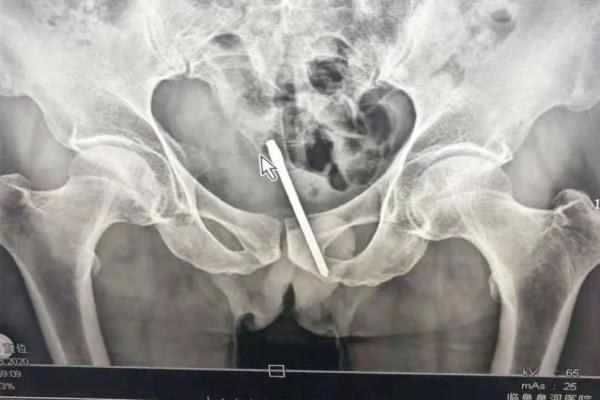

近日,據光明網報導,阜陽一比特60多歲的大爺因多天未排便,將一柄約10釐米長的起子塞進肛門內,結果不僅沒疏通,還把起子留在直腸中。

所幸就醫及時,醫生通過手術將异物取出。